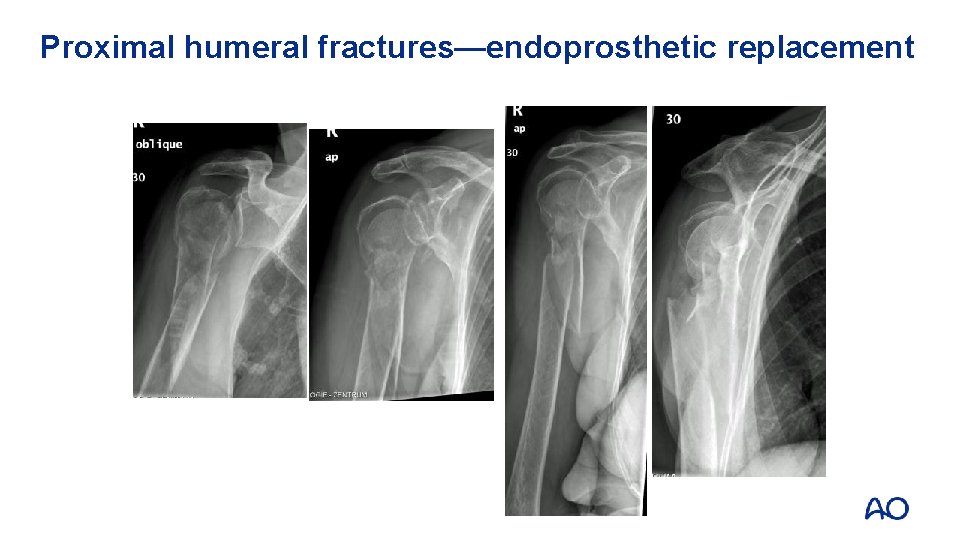

Proximal humeral fractures—endoprosthetic replacement

Proximal humeral fractures—arthroplasty

Proximal humeral fractures—arthroplasty Indications: • Head-split fractures • Thin shell • After failed osteosynthesis Goal: • Alleviate pain • Restore function

Arthroplasty versus nonoperative • Study results demonstrated a significant advantage in quality of life in favor of hemiarthroplasty in elderly patients with a displaced 4 -part fracture • Main advantage appeared to be less pain with no difference in range of motion